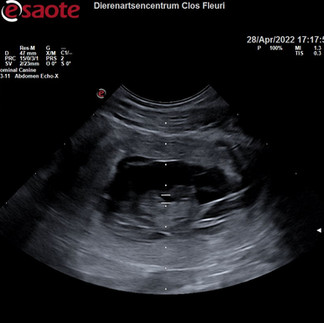

Buikje kreeg een beetje gel en dan ging de echoscoop erop.

nog geen seconde later, 'oh u heeft geluk!'

Ik keek naar het scherm en zag daar een vruchtje mooi in beeld.

Even naar het hartje geluisterd. Steeds opnieuw een prachtig moment.

In het flits was de echo voorbij, weer genoten van de pups te zien in het buikje.